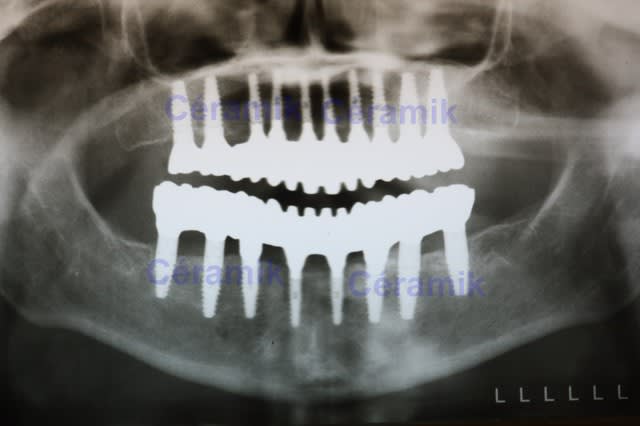

05/10/2011 à 01h41

Malheureusement, je ne fais pas (encore) de disk...

et pas bcp de "gros" cas...

mais je vient de terminer celui-ci...

Plus classique comme approche...1

8 implants et 6 bridges

--

Céramik

Les implants sont des Bio-Horizon TLR

En postérieur, des 4,6 mm

en antérieur, des 3,8 mm

La pano est un peu déformée, sorry.